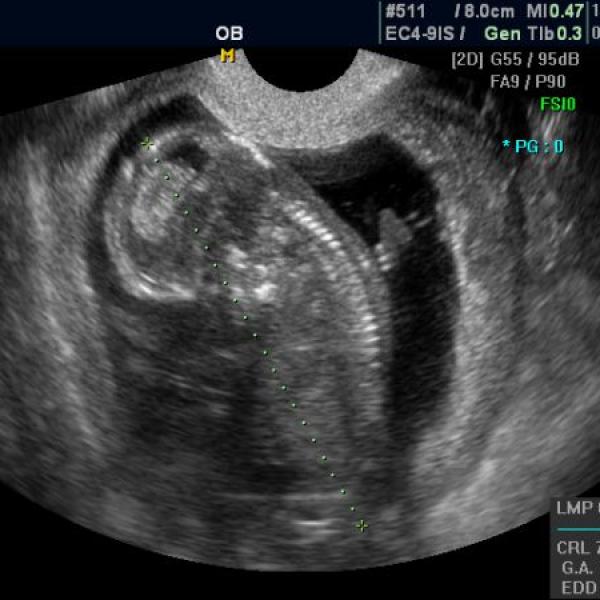

tak jsme dneska absolvovali NT screening...... byla jsem z toho docela vystrašená, ale nakonec vše dobře dopadlo. Celkové riziko nám vyšlo 1 / 13 100 takže radost veliká...

+ ještě přikládám utz ze 10tt